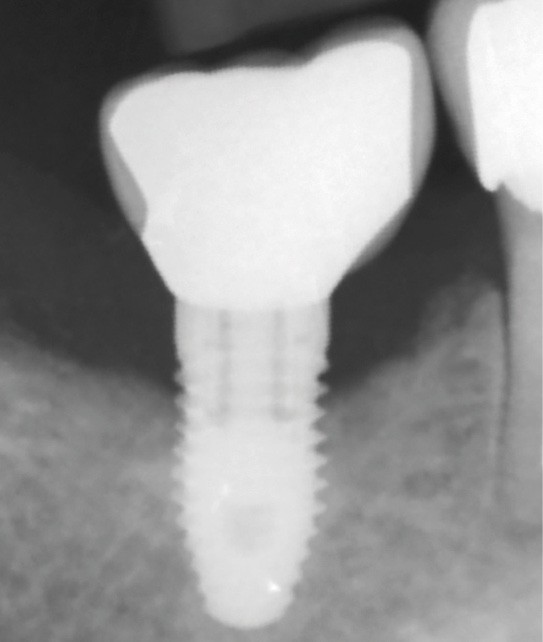

L’implant

- Péri-implantite sur l’implant 47, diagnostiquée en août 2022

- Poches de 6 à 7 mm

- Implant posé en 2017

- Nobel Replace Select RP (4,1 x 10 mm)